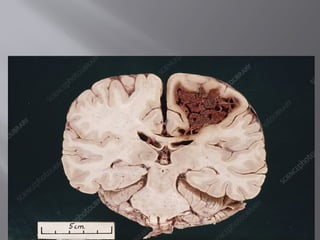

 CEREBRAL INFARCTION

 Also called ischemic stroke, a cerebral

infarction occurs as a result of disturbed blood

flow to the brain due to problems with the

blood vessels that supply it.

 A lack of adequate blood supply to brain cells

deprives them of oxygen and vital nutrients

which can cause part of the brain to die.

 CEREBRAL INFARCTION Also called ischemic stroke, a cerebral infarction occurs as a result of disturbed blood flow to the brain due to problems with the blood vessels that supply it.  A lack of adequate blood supply to brain cells deprives them of oxygen and vital nutrients which can cause part of the brain to die.